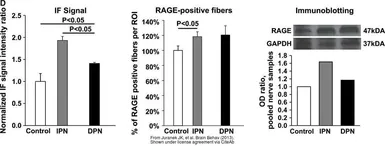

The data was published in the journal Brain Behav in 2013. PMID: 24363972